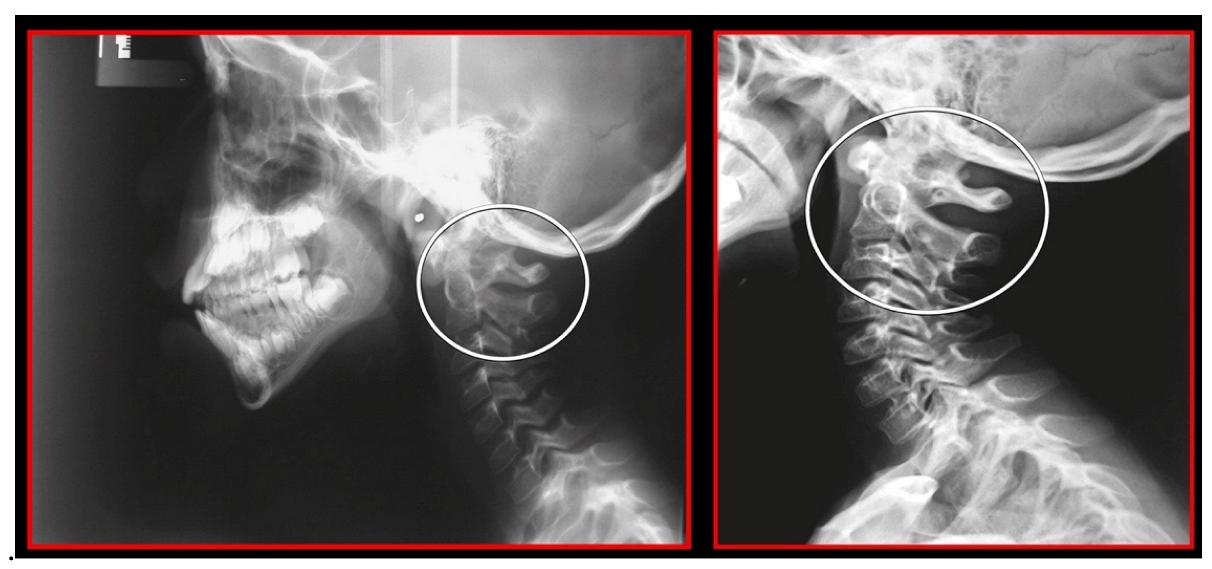

10.1. Neck X-ray

11.5. Axis and Atlas Derotation